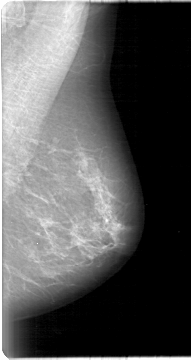

D_4011_1.RIGHT_MLO

RIGHT_MLO LINES 5311 PIXELS_PER_LINE 2521 BITS_PER_PIXEL 12 RESOLUTION 43.5 OVERLAY

FILE: D_4011_1.RIGHT_MLO.OVERLAY

TOTAL_ABNORMALITIES 1

ABNORMALITY 1

LESION_TYPE MASS SHAPE OVAL MARGINS OBSCURED

ASSESSMENT 0

SUBTLETY 4

PATHOLOGY BENIGN

TOTAL_OUTLINES 1

BOUNDARY